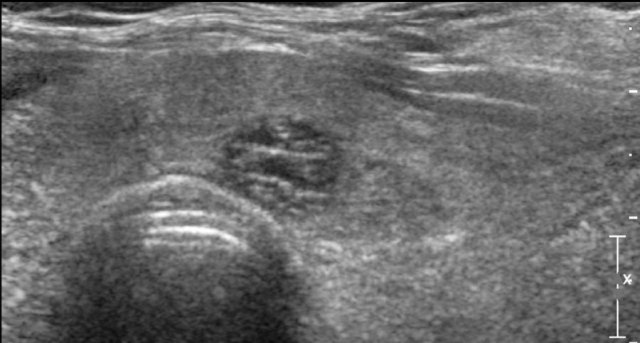

Ill-defined nodule.

Notice how only some small parts of the border of the nodule can be defined (arrow).

Most of its margin is indistinct from the thyroid parenchyma.

0 points in TI-RADS.